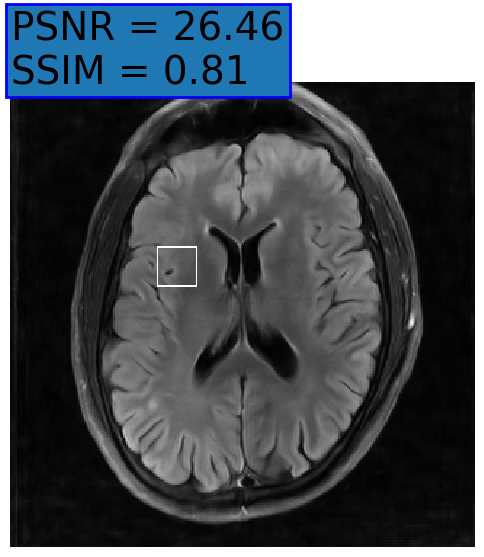

Figure 3: Reconstructions results. Rows 1 and 3: Examples of comparing the ground truth (GT) fully sampled image to the reconstructed images obtained by the three models (1-3), NPB-REC, baseline, E2E-VarNet trained with Dropout, and the NPB-REC std. map at accelerations R=4𝑅4R=4, R=8𝑅8R=8, respectively. Rows 2 and 4: The corresponding annotated ROIS of Nonspecific white matter lesions.

Fig. 3 presents examples of reconstruction results obtained by (1) our NPB-REC approach, (2) the baseline, and (3) Monte Carlo Dropout, for equispaced masks with two different acceleration rates R=4𝑅4R=4 and R=8𝑅8R=8. The reconstructed images predicted by the three models are smoother than the reference image. This is due to the fact that all the models were trained with SSIM loss, which tends to produce overly smooth reconstructions while preserving the diagnostic content and the anatomical features Sriram et al. (2020a). These images can be enhanced by dithering the image by adding a small amount of random Gaussian noise to produce a more textured reconstruction, as proposed in Sriram et al. (2020b).

Table 1 presents the mean PSNR and SSIM metrics, calculated over the whole inference set, for the three models. Our NPB-REC approach achieved significant improvements over the other methods in terms of PSNR and SSIM (Wilcoxon signed-rank test, pmuch-less-than\ll1e-4, except for SSIM values in line W, R=4𝑅4R=4 where they are roughly the same for NPB-REC and Baseline). The improvement in the reconstruction performance can be noted both quantitatively from the metrics, especially for masks with acceleration rate R=8𝑅8R=8, and qualitatively via the images of annotations, where our results show less smoothness than those obtained by Dropout.